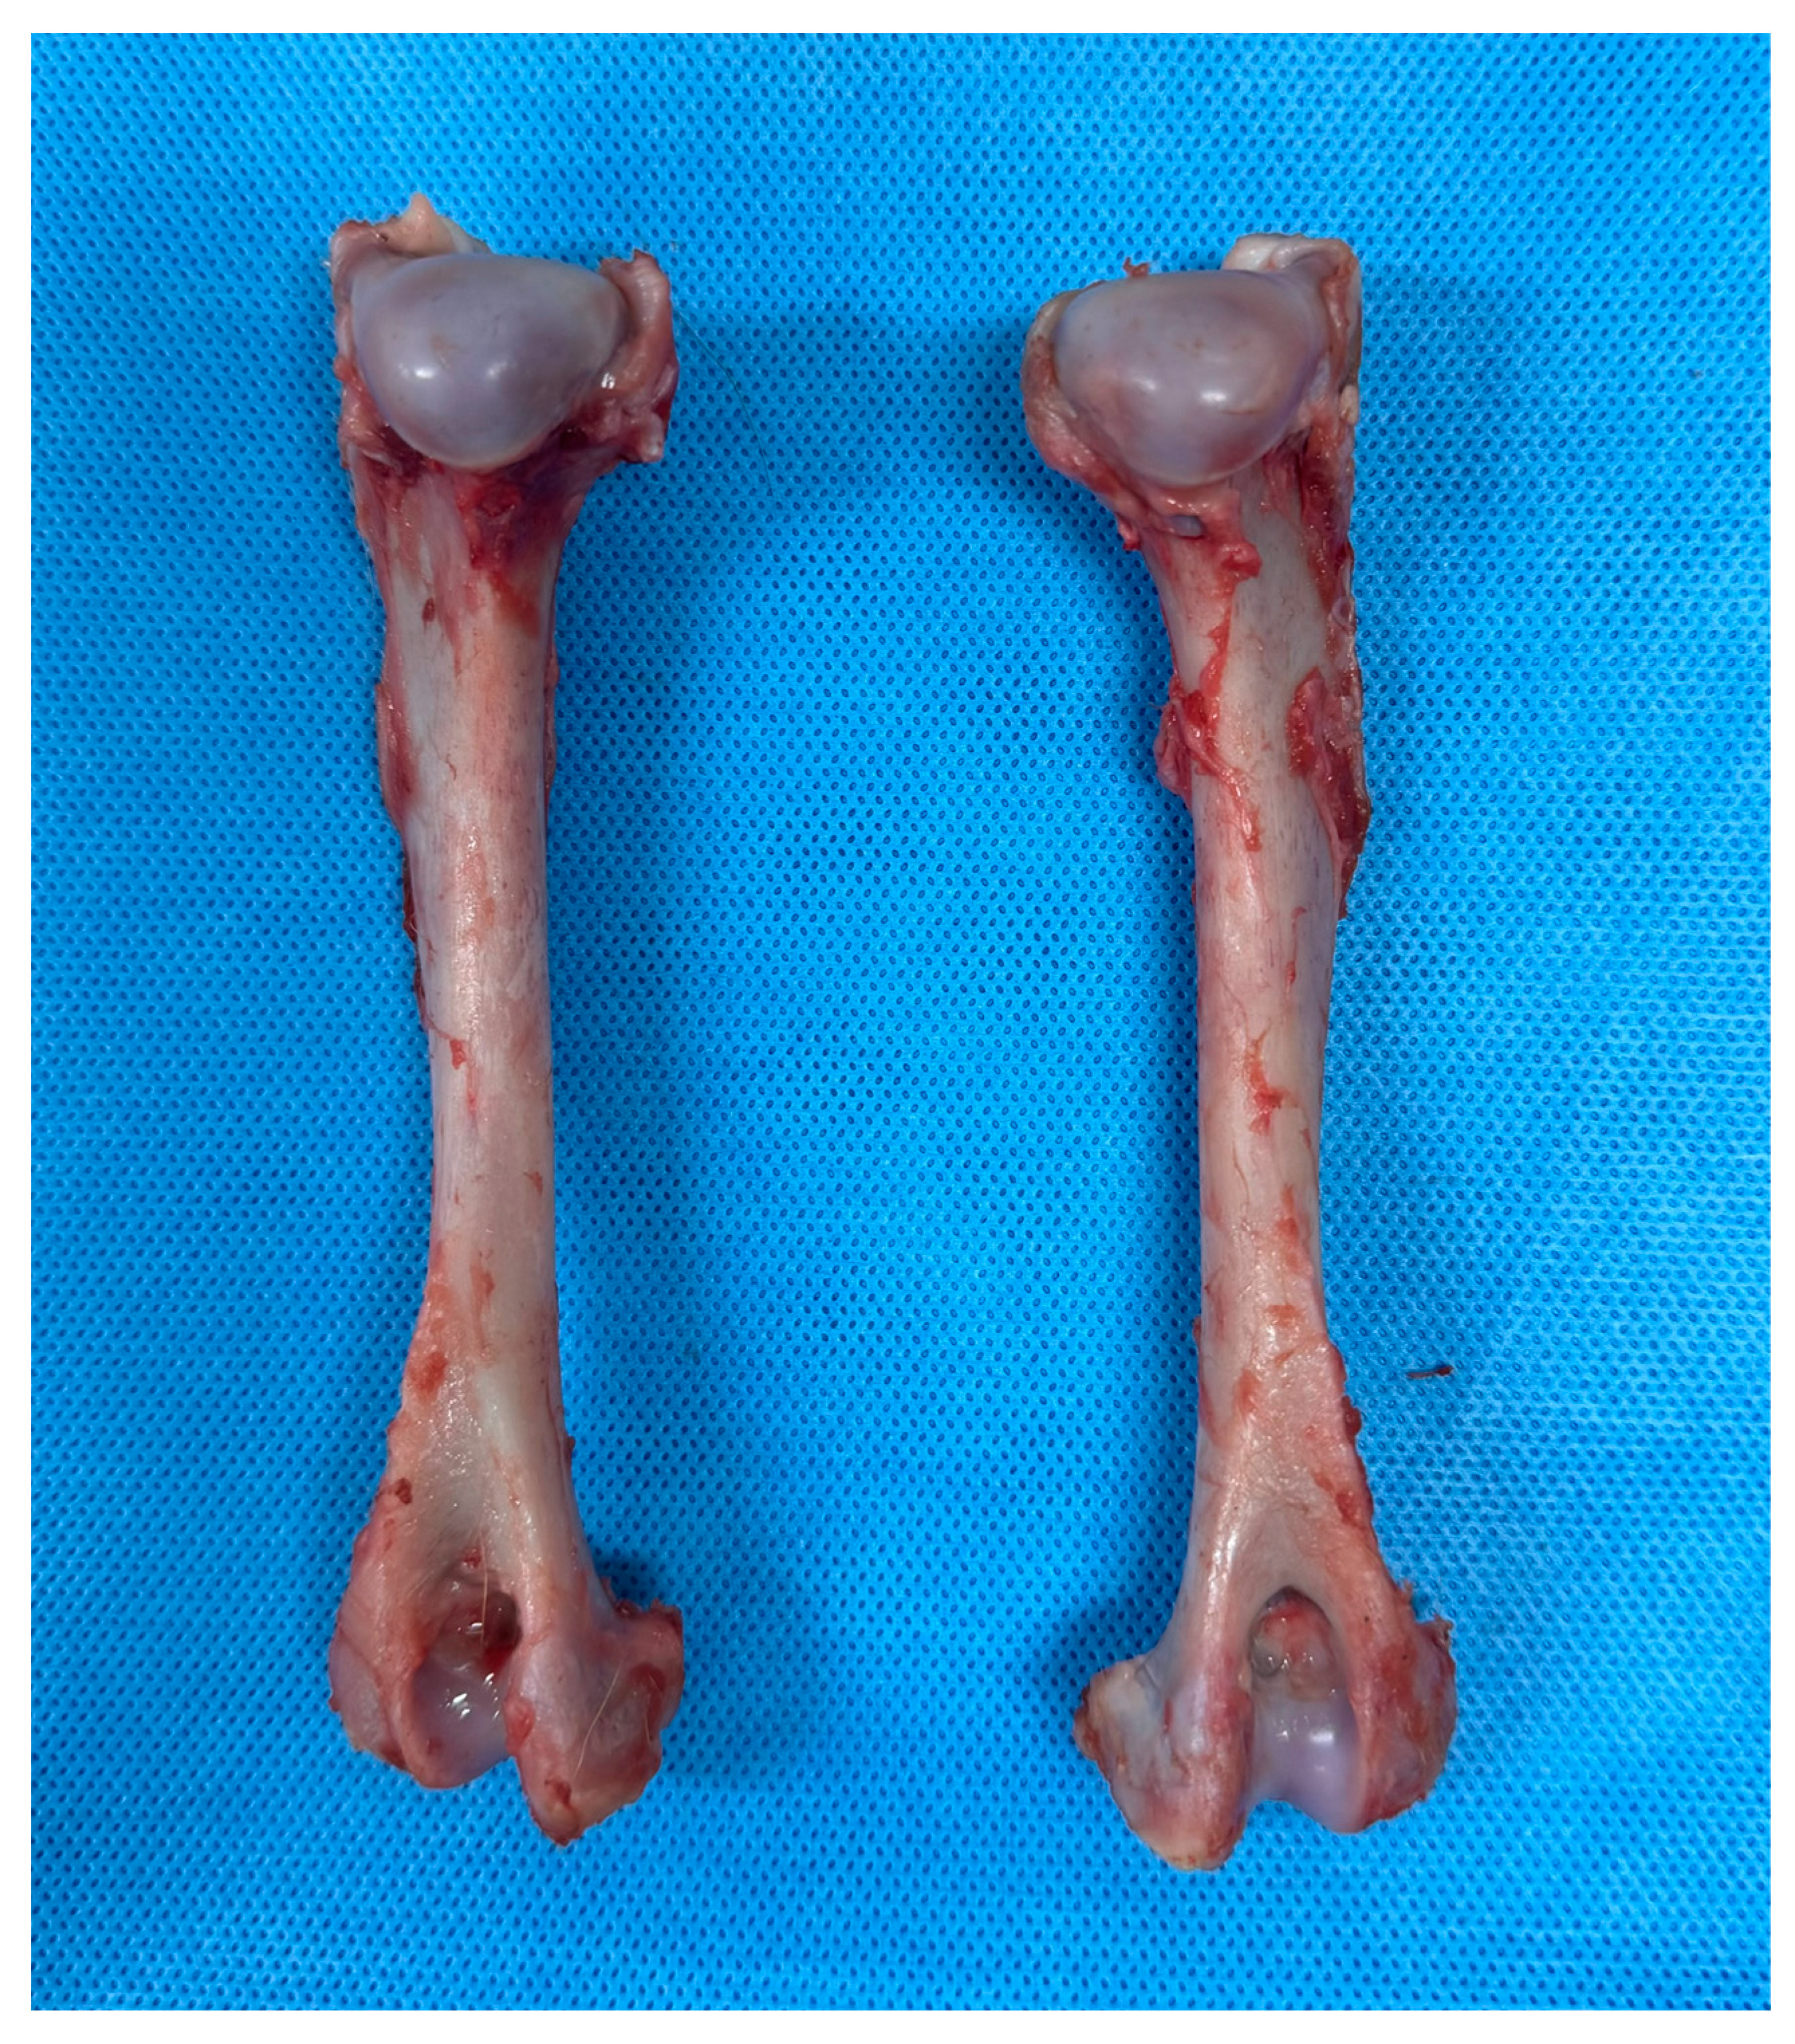

2.1. Cadaver Preparation

2.2. Implant Application